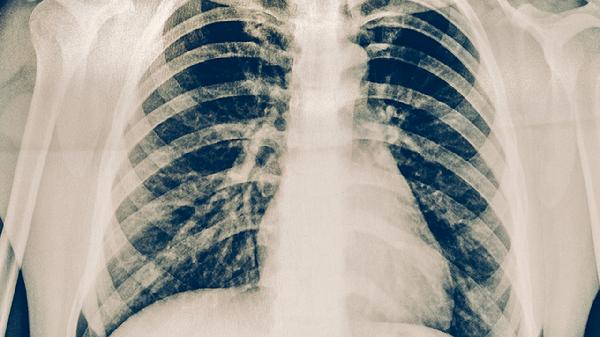

若红色凸起直径超过10毫米,或伴随水疱、坏死、淋巴结肿大、发热等症状,可能提示结核感染或强阳性反应。此类情况需结合胸部影像学检查、痰涂片等进一步评估。既往接种卡介苗者可能出现假阳性反应,而免疫功能低下者可能出现假阴性,需由医生综合判断。出现异常反应时应及时就医,避免自行处理。